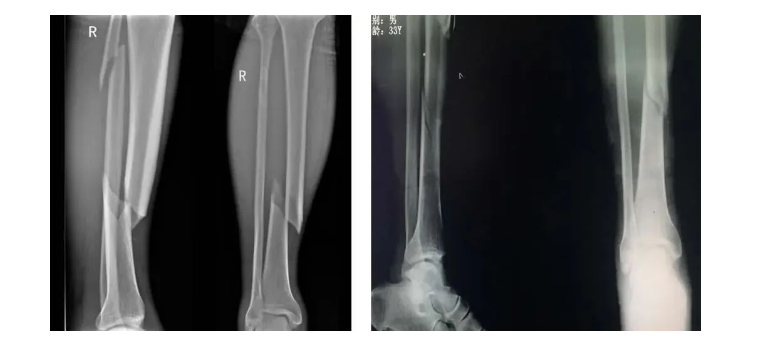

脛骨(gu)(gu)干是(shi)常(chang)見(jian)的(de)骨(gu)(gu)折(zhe)好發類型之(zhi)一(yi),占全身骨(gu)(gu)折(zhe)的(de)13.7%。脛骨(gu)(gu)下(xia)端具有(you)血(xue)運代償性(xing)不佳、軟組(zu)織覆蓋少等解剖特點(dian),一(yi)旦出(chu)現骨(gu)(gu)折(zhe),軟組(zu)織受損,局部血(xue)供不佳,將會增(zeng)加(jia)(jia)骨(gu)(gu)折(zhe)愈合(he)的(de)難度,加(jia)(jia)之(zhi)合(he)并腓骨(gu)(gu)骨(gu)(gu)折(zhe)概(gai)率高、穩定性(xing)不佳,選擇(ze)適宜(yi)的(de)手術方案十(shi)分必要。

脛(jing)骨干中(zhong)上段(duan)橫截面(mian)呈三(san)角形(xing)(xing),下(xia)1/3處橫截面(mian)呈四方形(xing)(xing)。中(zhong)下(xia)1/3交界(jie)處比較細,又是形(xing)(xing)態發生改變的(de)部位(wei),為骨折好發部位(wei)。

脛(jing)骨的前1/3僅有皮膚覆蓋沒(mei)有肌肉覆蓋,骨折時骨斷端易戳破皮膚形成開放性骨折,即(ji)使是閉(bi)合性骨折(zhe)大多數脛骨骨折(zhe)都合并皮膚和皮下組織損傷。脛骨中段缺少肌(ji)肉覆(fu)蓋,且脛腓骨周圍有四(si)個筋膜室。骨筋(jin)膜室綜合征(zheng)發(fa)生率(lv)高于其他(ta)骨折(zhe)。